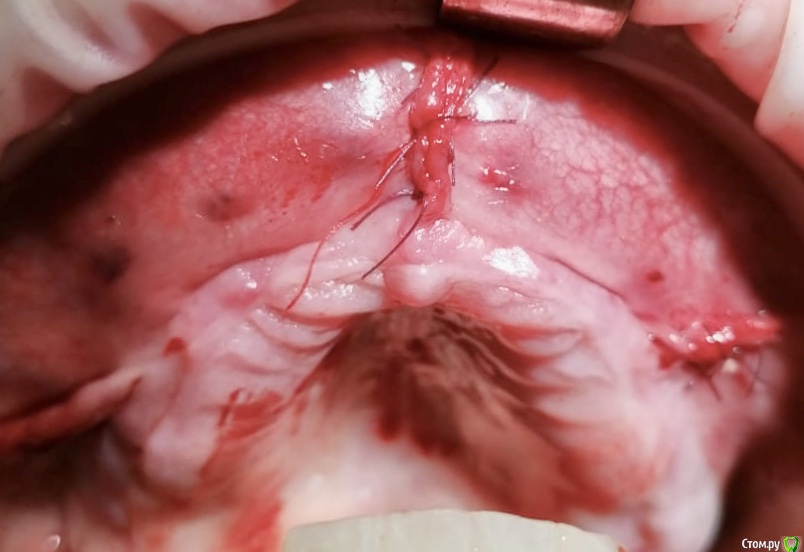

колесников Опубликовано 15 июня, 2020 Автор Поделиться Опубликовано 15 июня, 2020 Тоннельный графтинг фронт в/ч ,для поддержки мягких тканей губы и два открытых синуса vista доступ. 5г на все 4 Ссылка на комментарий

Evikrol Опубликовано 19 июня, 2020 Поделиться Опубликовано 19 июня, 2020 Расскажите что за швы во время введения графта? Их функция? Ссылка на комментарий

колесников Опубликовано 19 июня, 2020 Автор Поделиться Опубликовано 19 июня, 2020 Это я роллом раскрылся Ссылка на комментарий